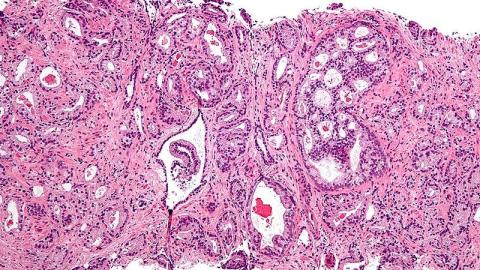

The U.S. Preventive Services Task Force is about to recommend that healthy men forgo being screened for prostate cancer with the familiar PSA blood test. Its recommendation is based on several human trials indicating that screening does not save lives. If a PSA level is high, for example, and the subsequent biopsy is positive for cancer, men who then receive treatment “do not have a lower death rate from prostate cancer than people who were never screened,” says Marc Garnick, prostate cancer expert at Harvard’s Medical School.

It is important to bear in mind that the Task Force’s recommendation applies only to healthy men. Those with a history of prostate cancer in their family or African American men, who are at higher risk of contraction, should continue to be screened. “In the end, we urgently need a screening test that can distinguish well between prostate cancers that will become life-threatening and those that will not,” says Garnick, “and we need treatments that come with fewer risks of severe side effects.”